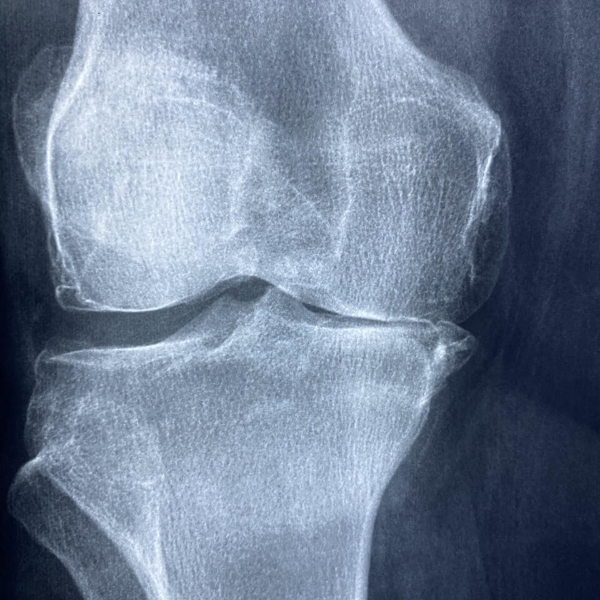

2) 사전 검사

수술 전에는 혈액검사, X-ray, MRI, 심전도 등 정밀 검사를 통해 환자의 전반적인 건강 상태와 무릎 관절 상태를 확인합니다. 이를 통해 안전한 수술 계획을 세울 수 있습니다.